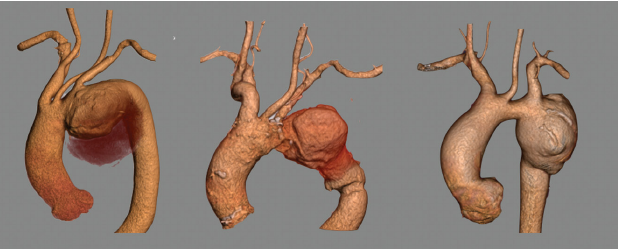

The aorta is the largest artery in the body that starts like a spout from the heart, runs down the chest into the abdomen, and gives off branches to every organ in the body.

An aneurysm is a bulge or a ballooning out of the artery due to weakness in the vessel wall. Rupture of the weakened wall invariably leads to instantaneous death. It’s the equivalent of shooting someone in the heart.